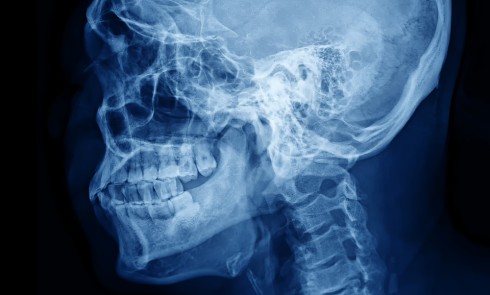

Article réservé à nos abonnés Dysfonctionnements temporo-mandibulaires : mythes et réalités

Le terme dysfonctionnement temporo-mandibulaire (DTM) englobe une trentaine de troubles musculo-squelettiques (TMS), douloureux ou non, qui impliquent les articulations temporo-mandibulaires...

Séance CNO : “Docteur, ma mâchoire craque” : quelle conduite à tenir ?

Durée : 03:53 Faut-il forcément traiter les bruits articulaires ? Tout d’abord, il est nécessaire de faire un…